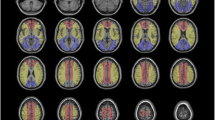

There were two types of hyperperfusion observed in this study. The first type is a significant perfusion signal increase in the surgery side that the absolute CBF value exceeds the value of the contralateral side (a representative case in Fig. 2). The second type is an evident low perfusion area in preoperative ASL, and after carotid surgery, the CBF increase filled up the low perfusion area, but the postoperative absolute CBF was comparable to the contralateral side (a representative case in Fig. 3).

Hyperperfusion type 1. A patient with right-side carotid stenosis. (a–c) Preoperative perfusion territories on territory-ASL. (d) Preoperative CBF of ASL reveals reduced CBF on the right watershed area. e Postoperative CBF of ASL reveals hyperperfusion on perfusion territory of the right internal carotid artery, and signal is much higher than the contralateral side

Hyperperfusion type 2. A patient with right-side carotid stenosis. (a–c) Preoperative perfusion territory on territory-ASL. (d) Preoperative CBF of ASL reveals reduced CBF on the right watershed area, and intravascular high signal was seen on low perfusion area (arrow), indicating long ATT. e Postoperative CBF of ASL reveals regional CBF increase > 100%, but the mean perfusion signal on the right hemisphere is only a little higher than that of the contralateral side

CHS case 1. (a) Preoperative CTA indicates right ICA occlusion and severe stenosis of the left ICA. (b) Preoperative ASL reveals regional reduced CBF and higher signal heterogeneity on the right hemisphere. (c–e) Preoperative territory-ASL shows no perfusion of the right ICA and collateral flow from the left ICA and posterior circulation. Patient underwent left-side CAS and presented with seizure on the 7th postoperative day. (f) CT scan reveals intracranial hemorrhage on the left side. (g) Susceptibility-weighted imaging (2 months after surgery) reveals hypointensity in the sulci of the left hemisphere

CHS case 2. (a) Preoperative MRA reveals right A1 missing. (b–d) Preoperative perfusion territories showed by territory-ASL. The patient complained headache and soon developed into light coma. (e) Emergency CT demonstrated diffused edema of the left hemisphere. (f–h) Postoperative perfusion territories revealed by territory-ASL (3 months after surgery), no identifiable change compared with preoperative territory-ASL